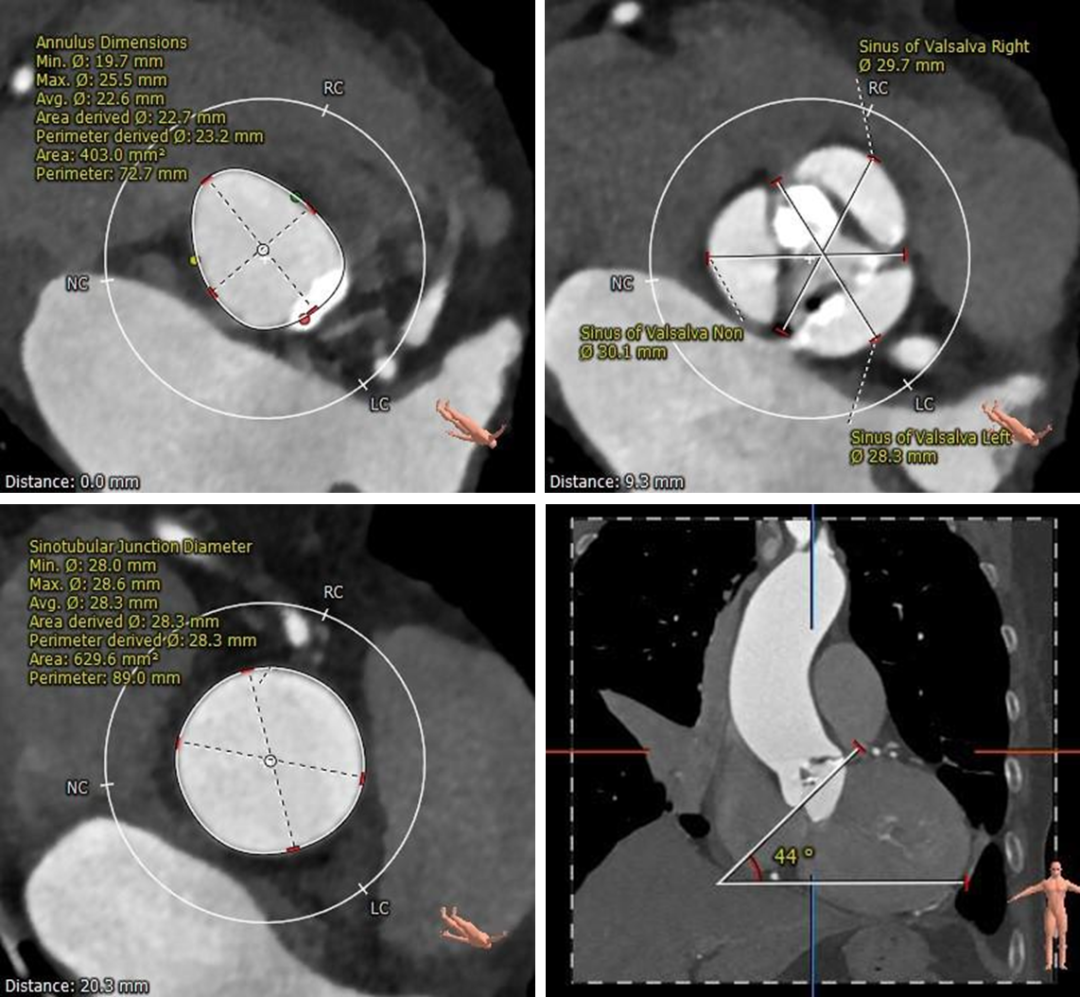

主动脉根部测量:

三叶式瓣,瓣叶增厚,可见钙化融合,非横位心。

冠脉测量:

右冠开口高度可左冠开口偏低(11.5mm),左冠窦瓣叶冗长(16.1mm)。